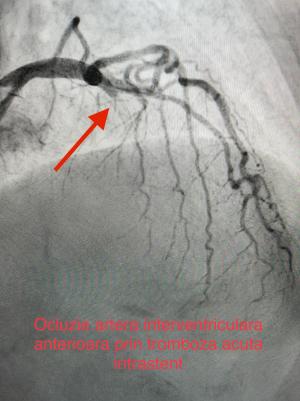

O intervenție medicală de urgență pentru salvarea unei paciente care suferise un stop cardiac a avut loc la Spitalul de Urgență Galați.

Pacienta a fost resuscitată, iar imediat echipa medicală a efectuat o coronarografie și a intrat în operație pentru realizarea mai multor proceduri de cardiologie intervențională.

„A fost un caz rar, având în vedere istoricul medical al pacientei, dar cu ajutorul medicilor și a procedurilor de cardiologie intervențională pacienta se simte bine, fiind deja externată. Felicitări întregii echipe medicale”, a transmis Costel Fotea, președintele CJ Galați.

La Galați, intervențiile de montare de stenturi sau de stimulatoare cardiace sunt gratuite, cu sprijinul financiar al Consiliului Județean.